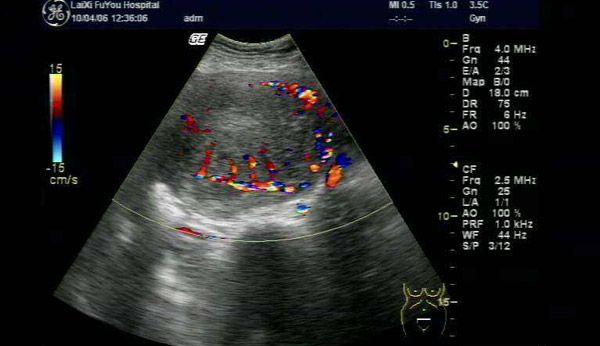

子宫腺肌病超声图像